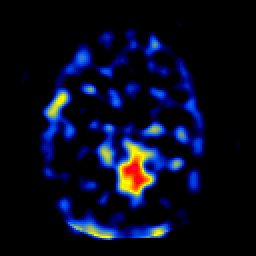

SPECT TL Study #6 -- Slice #32

[Home][Help][Clinical][Tour 1][Tour 2][Tour 3] Slice 32